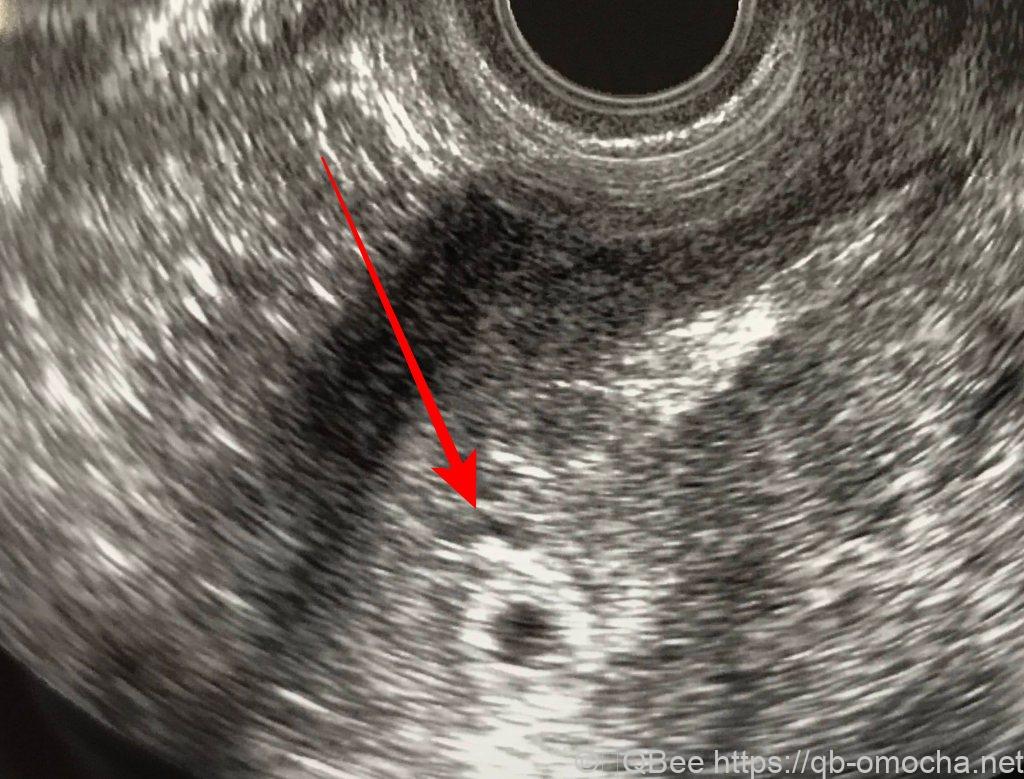

D14:卵泡檢查(陰部超音波)

卵泡檢查(陰部超音波)檢查流程

日本的陰部超音波檢查比較簡單,坐在檢查的椅子上後,醫生可以轉動調整椅子高度方向等等,所以我只要下半身脫掉,坐在檢查的椅子上,讓醫生隔著簾子檢查,比較不尷尬。

超音波的探頭會深入陰道內,醫生會調整角度並拍照。過程中只有剛放進去的時候有點異物感,但由於拍照時間有點久,很緊張。

我月經週期長一些(30-31天),所以這天超音波檢查有卵泡,醫生說生孩子的好時機是D17。子宮有息肉,但不影響。醫生說明月經可能來的時間,提到如果月經遲到一週,就來看醫生;如果月經來了,結束後兩週後再來。

醫生沒有提到要看第二次卵泡,也沒說卵泡的狀況。所以自己問了是哪一邊的卵巢及大小,醫生才說左邊卵巢有1.4公分的卵泡(剛好是阻塞的那一邊)…日本醫生都很省話?!

D37(第五週):終於熬到月經遲到一週的時間,在家用驗孕棒確認時,第二條線超快就出現了,根本不用等待,也不需要用晨尿就可以看到。我真的懷孕了嗎!?下午去婦產科報到,醫生先請我驗尿並照了陰道超音波,有看到小小的圓球,但沒有看到胎,所以又請我下週再來。花費1810日幣。

這次陰道超音波也只看到囊沒有胎,但有正常長大且非子宮外孕,讓我們鬆了一口氣,下週再來一次。

第七週:這次依舊是陰道超音,可喜可賀的是終於看到寶寶的心跳了!萬歲!而我也準備要回台灣待產了。

日本的產檢雖然不像台灣可以聽心跳聲,但醫生特別把簾子拉開讓我看看寶寶小小的心跳,真的很感動。